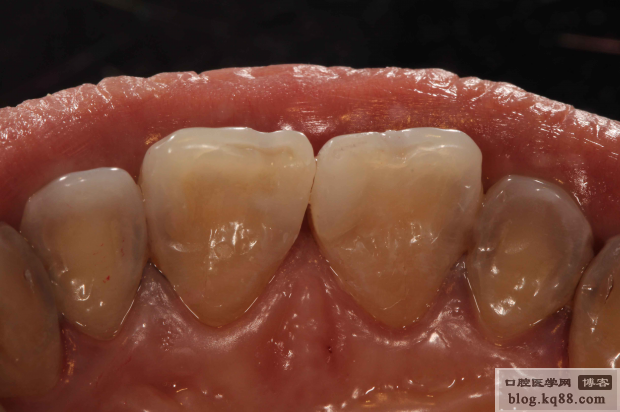

充填完成

隔日高光澤度拋光

隔日高光澤度拋光黑白照

術(shù)后唇側(cè)